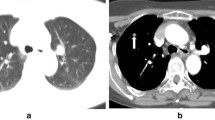

A 52-year-old man with suspected primary lung malignancy. a The intraprocedural non-contrast CT image (using mediastinal soft tissue window) showed a heterogenous mass in right upper lobe. b 18F-FDG PET/CT imaging showed heterogeneous uptake (SUVmax 10.2) in the mass with periphery hypometabolism. c CT and prior PET/CT fused image showed the biopsy needle punctured into hypermetabolic region of the mass. Surgical resection showed poorly differentiated lung adenocarcinoma with atelectasis

A planning CT scan (10-cm range) was performed before percutaneous needle insertion, and then the biopsy system including introducer needle (Cook Incorporated) and BioPince™ full core biopsy instrument (Argon medical devices, INC) was introduced in a stepwise manner under the guidance of images (CT images alone or CT and PET/CT fused images). An appropriate puncture point on a patient’s skin was marked to determine the shortest needle entry route while avoiding the inclusion of bullae and vascular structures. After local anesthesia with 2% lidocaine, a 10-cm-long 17-gauge percutaneous introducer needle was then advanced to puncture from the skin on the marked point without penetrating the parietal pleura. After confirming the direction of the tip of the puncture needle by the second CT scan (1.6 cm range), the needle was advanced further into the lesion (hypermetabolic area on fused images). Then the third CT scan was performed to confirm the final position of the tip of the needle before obtaining specimens coaxially. Two to three specimens were collected by BioPince™ full core biopsy instrument and subjected to histological evaluation for specific diagnosis (Figs. 1, 2). Finally, the fourth CT scan (the entire lung) was performed to rule out the presence of possible complications (e.g. pneumothorax, intrapulmonary hemorrhage, hemothorax, air embolism, etc.) after pulling out introducer needle. The CT-guided biopsy method was consisted with our previous studies. [15, 16] The severity of procedural complications was evaluated according to the Society of Interventional Radiology Standards of Practice Committee classification of complications [17], and procedure duration (defined as the interval time between the initial scout image and the end of the final CT scan) was also recorded. In addition, a repeat biopsy was considered when the patient’s clinical condition was obviously inconsistent with initial biopsy results (two patients) or when chemotherapy or targeted therapy regimens need to be adjusted (twenty patients). However, only the initial procedure result was recorded and analyzed in this study.